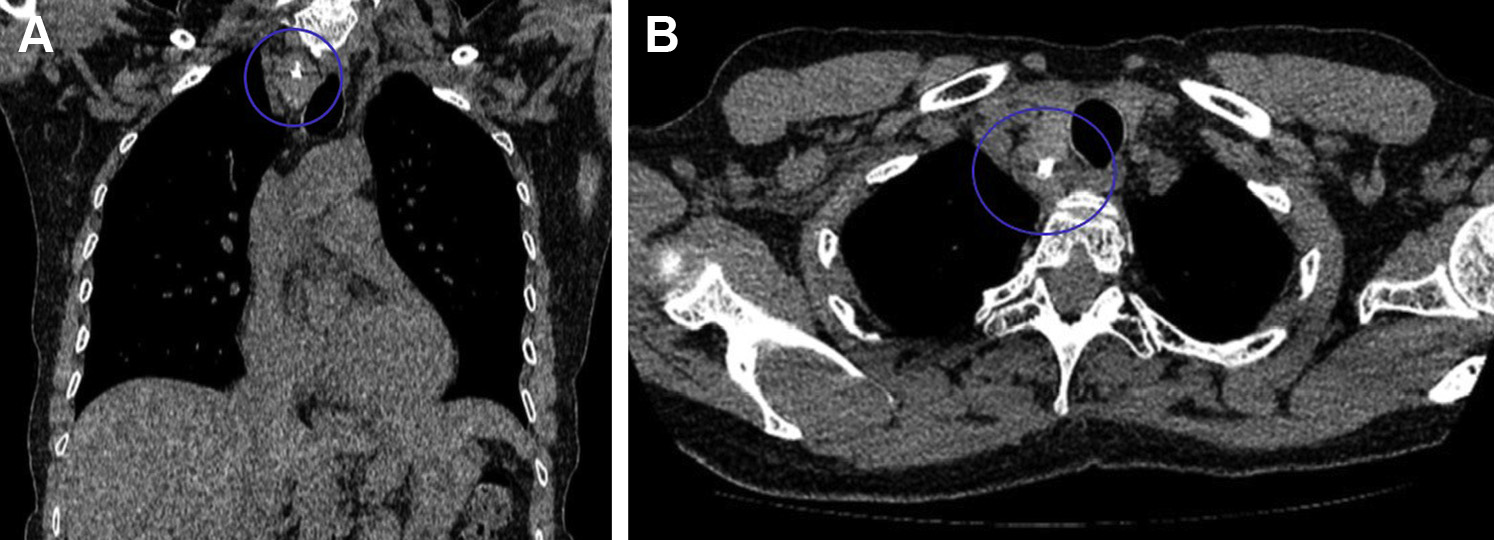

。胸部HRCT显示肺实质正常;右上气管旁有一个2.1×2.3cm的肿块,肿块不均匀,包含多个粗钙化灶(图1A, 1B)。气管稍微向左偏离,未侵及邻近肿块。核医学摄取和扫描证实肿块源于甲状腺。腺体中的总摄取量、促甲状腺激素水平在正常范围内。超声显示甲状腺不均匀,延伸至右侧胸骨后。

图1 A.冠状位胸部CT扫描(纵隔窗)显示右上气管旁2.1×2.3 cm肿块,含粗钙化灶(圆圈)。B.轴位胸部CT扫描(纵隔窗)显示不均匀肿块,气管轻微向左偏移(圆圈)。